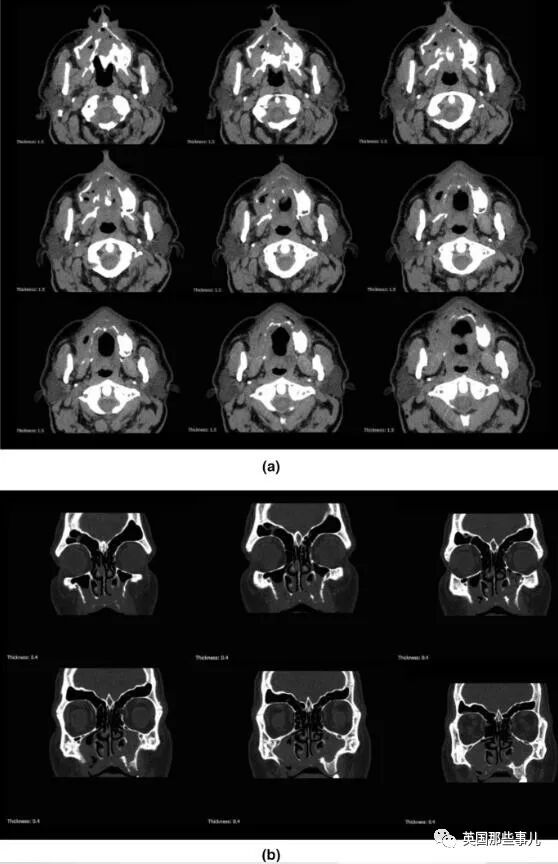

通過CT斷層掃描和核磁共振檢查,醫生們發現他的兩側上顎竇分別出現中度和輕度陰影,周圍組織也有浸潤,

但視力正常,也沒有毛霉菌(Mucormycosis)感染的跡象。